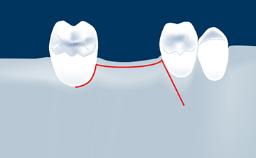

In this short microlearning module on digitally guided sinus floor elevation, we delve into a specialized aspect of the digital workflow for implant-guided surgery, focusing on the use of digital guides in the sinus floor elevation technique.

• understand the rationale and advantages of utilizing digital guides for sinus floor elevation (SFE)